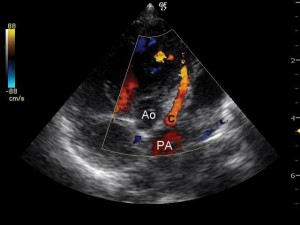

Evoluţia imediat postoperatorie a fost fără complicaţii, sugarul revenind în secţia de cardiologie pentru recuperare. Condiţiile generale erau ameliorate, notându-se chiar şi o uşoară creştere ponderală. Controalele ecocardiografice succesive au evidenţiat însă o dilataţie graduală a ventriculului stâng cu afectarea progresivă a funcţiei sistolice şi apariţia ulterioară a unei insuficienţe mitrale severe. Nu a putut fi vizualizată originea arterei coronare stângi din aortă, în plus notându-se flux bidirecţional în artera coronară descendentă anterioară la examenul Doppler color, ridicând suspiciunea de origine anormală a arterei coronare stângi (Figura 3). Presiunea pulmonară se redusese semnificativ (presiunea pulmonară medie a scăzut de la 40 mmHg la 21 mmHg), iar la nivelul septului interatrial nu exista şunt rezidual. Electrocardiograma evidenţia semne de ischemie miocardică, inexistente pe electrocardiogramele de dinainte de intervenţie: segment ST subdenivelat descendent în precordialele stângi şi unde T negative simetrice în precordialele drepte (Figura 4).

Figura 3. Ecocardiografie transtoracică incidenţă parasternal ax scurt: origine anormală a arterei coronare stângi. Ao: aortă, P: pulmonară, C: artera coronară.

În aceste condiţii sugarul a fost din nou transferat în serviciul de chirurgie cardiacă. S-a realizat cateterismul cardiac care a confirmat suspiciunea ecocardiografică de origine anormală a arterei coronare stângi din artera pulmonară (Figura 5). S-a reintervenit chirurgical. Intraoperator s-a observat originea arterei coronare stângi la nivelul bifurcaţiei arterei pulmonare, posterior, având un trunchi comun destul de lung. S-a realizat implantarea arterei coronare stângi în aortă. Evoluţia post-reintervenţie a fost bună, cu instalarea unei bune creşteri ponderale ulterior. Ecocardiografia a ilustrat noua origine a arterei coronare stângi din aortă (Figura 6), absenţa şuntului la nivelul septului interatrial şi ventriculul stâng revenit la o contractilitate bună (Figura 7); insuficienţa mitrală era uşoara şi persista defectul septal interventricular muscular apical mic. Electrocardiograma s-a normalizat (Figura 8). La 3 ani de la intervenţie copilul este asimptomatic şi are o dezvoltare psihosomatică corespunzătoare vârstei.

Figura 7. Ecocardiografie transtoracică incidenţă parasternal ax scurt: vizualizarea originii corecte a arterei coronare stângi din aortă.